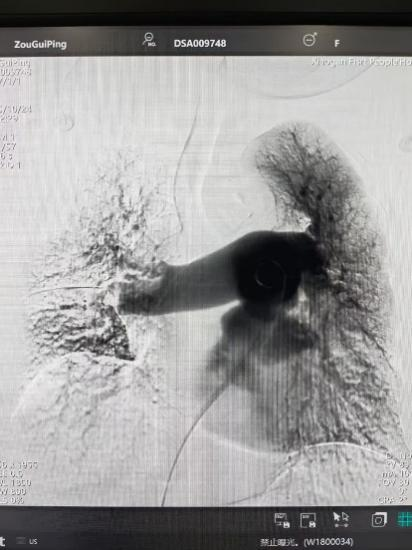

術(shù)后

手術(shù)在局部麻醉下進(jìn)行,團(tuán)隊(duì)通過(guò)股靜脈穿刺,將專用抽栓導(dǎo)管精準(zhǔn)送達(dá)肺動(dòng)脈栓塞部位,利用負(fù)壓抽吸技術(shù)成功清除大量血栓;隨后,在血栓局部精準(zhǔn)灌注溶栓藥物,進(jìn)一步溶解殘余血栓,恢復(fù)肺部血流灌注;同時(shí),為防止下肢深靜脈血栓再次脫落引發(fā)肺栓塞,團(tuán)隊(duì)為患者置入下腔靜脈濾器,整個(gè)手術(shù)歷時(shí)約1小時(shí)。術(shù)后,鄒婆婆呼吸困難癥狀即刻得到緩解,血氧飽和度顯著提升,右心負(fù)荷明顯減輕,目前身體狀況正在逐步恢復(fù)中。